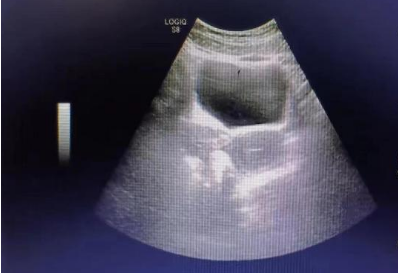

专科检查:外阴发育正常;肛门指诊:直肠黏膜光滑,盆腔右侧可触及囊实性肿物,活动度差,触痛。超声检查:子宫大小约3.5 cm*4.1 cm*3.7 cm,内膜厚约1.4 cm;右侧附件区见大小约7.2 cm*6.3 cm*5.2 cm囊实性回声,周边可见血流信号;左侧附件区见大小约1.5 cm*1.0 cm囊性回声,边界清,透声可;子宫后方可见厚约1.7 cm液性暗区。

主诉:发现卵巢肿物半年,2023-01-26第二次入院。超声检查:子宫大小约3.5 cm*4.1 cm*3.7 cm,内膜厚约1.4 cm;右侧附件区见大小约7.2 cm*6.3 cm*5.2 cm囊实性回声,周边可见血流信号;左侧附件区见大小约1.5 cm*1.0 cm囊性回声,边界清,透声可;子宫后方可见厚约1.7 cm液性暗区。肿瘤标志物:HE4:39.4 pmol/l;CA125:41.35 U/ml(↑);CA199:46.75 U/ml(↑)。术中情况:子宫正常大小,部分肠管及大网膜粘连于宫底及后壁;右侧卵巢囊肿直径约7.0 cm,包膜完整,与子宫后壁及同侧阔韧带后叶粘连,封闭子宫直肠窝。剔除囊肿过程中囊肿破裂,可见咖啡色粘稠血性液体流出,囊肿单房,内壁光滑。